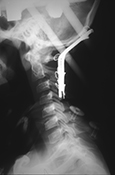

Nearly Decapitated Child Recovers (May 1989)

Miracle Surgery Saves Boy Who Had Head Cut Off (Star Magazine, June 1989)